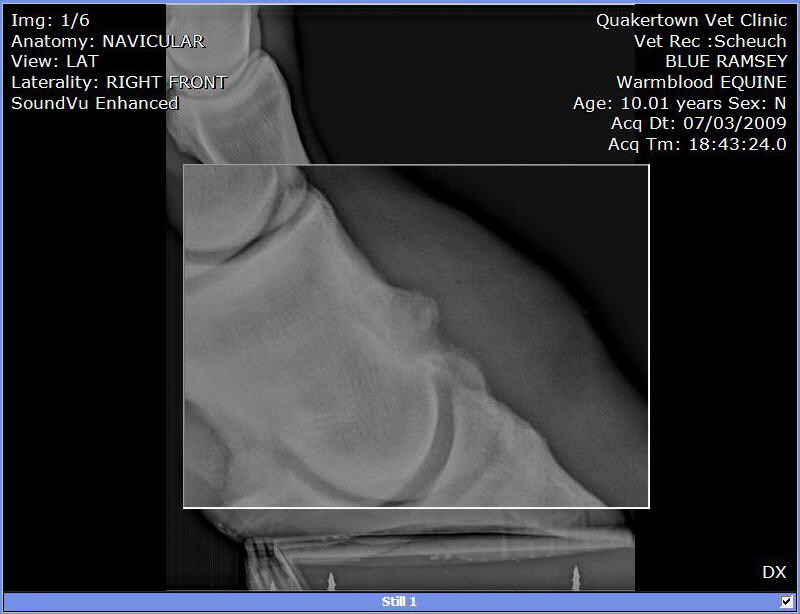

We put shoes on. Last week the farrier replaced them. He used a hoof tester checking of abscess or some reason for his slight limp. Since that day he as barely been able to walk. So, we called in the Vet to have him tested. A block in the heel helped him quite a bit. A block low in front and he was able to walk and trot without a limp.

X-rays:

I can see these are not images of a healthy hoof.

Among the many abnormalities the most important is the radiographs are clear for DJD of the coffin joint or what is often called low ringbone. No the hoof testers did not aggravate it, I suspect flexion of the joint during the exam did. You will find much information on this condition and what to expect at Diseases of Horses » Lameness » Diseases of the Lower Limb » Ringbone.

I can not read xrays to save my life, but I couldn't help feeling that this horse's foot was out of balance (from Image 3/6). I can't tell if its the way his foot is positioned on the plate, but he sure looks lopsided to me.

I would get his shoes off and get him back in balance ( to me he looks low on the outside and high on the inside. I'd be able to tell better if I could see the foot from the bottom to see which way the frog is leaning. I'd try to keep him as simple as possible at least for a few days to see how he handles being barefoot.

As rtrotter noted above the horse is either standing oddly or the foot is unbalanced from side to side in the above radiographs, careful management of balance and breakover could help this horse be as comfortable as possible.

Do the images suggest that the side bone has broken off?

No Guy it does not indicate it. Though we cannot say for sure this is a common appearance of a focal area of calcification for more on this see Diseases of Horses » Lameness » Diseases of the Hoof » Side Bone and the Collateral Cartilages.